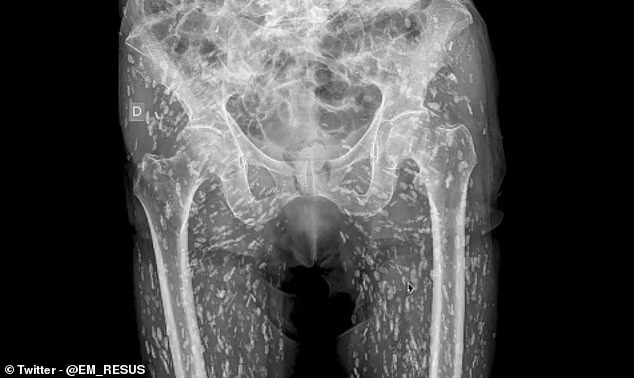

24/01/2025 18:31Bác sĩ bàng hoàng vì ảnh X-quang vô số sinh vật bên trong cơ thể bệnh nhân, nguyên nhân là bởi thói quen thường thấy khi ăn uống

Bệnh nhân thực tế không hề hay biết về tình hình sức khỏe mà chỉ nhập viện để chụp X-quang kiểm tra chấn thương sau khi bị ngã.

"Nang sán xuất hiện khắp mọi nơi, nhiều vô kể đến mức không đếm nổi. Nang sán có thể di chuyển trong cơ thể. Đối với bệnh nhân này, nang sán đã xuất hiện ở mô mềm tại vùng hông và chân," bác sĩ Ghali giải thích.

Bác sĩ Ghali giải thích bệnh nhân bệnh nhân đã ăn thịt lợn sống hoặc chưa nấu chín có ấu trùng giun sán. Ấu trùng này dường như đã xâm nhập vào cơ thể bệnh nhân, tạo nên các nang nhỏ có thể gây nhiễm trùng.

Nhiễm trùng sán lợn có thể xảy ra sau khi bênh nhân ăn phải trứng sán trong thịt lợn nhiễm sán hoặc chưa nấu chín. Bệnh ấu trùng sán lợn có thể gây nguy hiểm khi xảy ra ở não hoặc hệ thần kinh, gọi là nhiễm ấu trùng sán dải heo hệ thần kinh trung ương.

Bệnh ấu trùng sán lợn và nhiễm nhiễm ấu trùng sán dải heo hệ thần kinh trung ương phổ biến nhất tại các cộng đồng nông nghiệp ở các nước đang phát triển, theo Daily Mail.

"Tiên lượng bệnh ấu trùng sán lợn và nhiễm nhiễm ấu trùng sán dải heo hệ thần kinh trung ương thường khá tốt, nhưng vẫn có nhiều ca tử vong," bác sĩ Ghali cho biết, lưu ý rằng ước tính mỗi năm có khoảng 50 triệu ca nhiễm và 50.000 trường hợp tử vong.

Bác sĩ Ghali nhấn mạnh ca bệnh khiến ông muốn nhắc nhở tất cả mọi người "cố gắng giữ gìn vệ sinh, rửa tay sạch sẽ, và không được ăn thịt lợn sống hay chưa nấu chín trong bất cứ tình huống nào".

"Bài học rút ra là phải cố gắng giữ gìn vệ sinh, luôn rửa tay và không bao giờ ăn thịt lợn sống hoặc chưa chín trong bất kì tình huống nào," bác sĩ Ghali nói thêm.